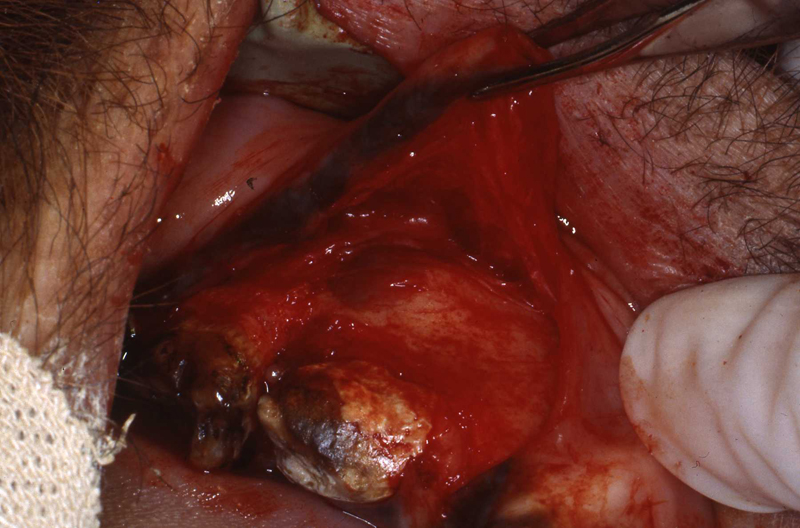

Fistula explored

Fistula exposed

Fistula being repaired

Fistula exposed, tensionless flap